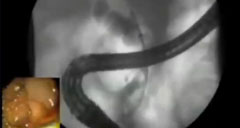

Extracción de cálculos asistida por dilatación (DASE) por el Dr. Amit Maydeo

El video muestra el dilatador de balón guiado por cuerda CRE™ para la dilatación endoscópica.

Extracción de cálculos asistida por dilatación (DASE) por el Dr. Amol Bapaye

El video muestra el dilatador de balón guiado por cuerda CRE™ para la dilatación endoscópica.

Animación de la extracción de cálculos asistida por dilatación (DASE)

La animación muestra el dilatador de balón guiado por cuerda CRE™ para la dilatación endoscópica.

Extracción de cálculos asistida por dilatación (DASE) por el Dr. Abhitabh Patil, MD

El video muestra el dilatador de globo guiado CRE ™ para la dilatación endoscópica.

Extraction de calculs assistée par macro dilatation (DASE) avec un ballon CRE™

Procédure d'extraction de calculs biliaires avec un ballon CRE par Dr Arthur Laquière et Dr Christian Boustière .